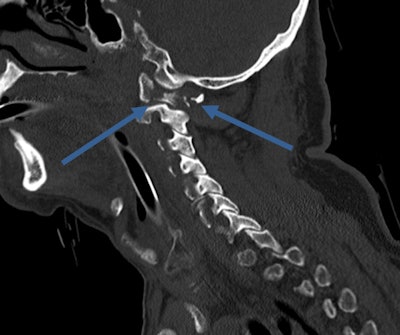

Always remember that numerous fractures can come from seemingly minor accidents. In this case, a 70-year-old fell downstairs, causing a fracture of the C1 ring. Image courtesy of Dr. Elizabeth Dick, first published in ECR Today newspaper."When I was first on call, we had a buddy system, and the more experienced junior doctors would give us their phone number so we could call at any time overnight," she said. "And then, of course, a few years later, it's your turn to [do the same]."